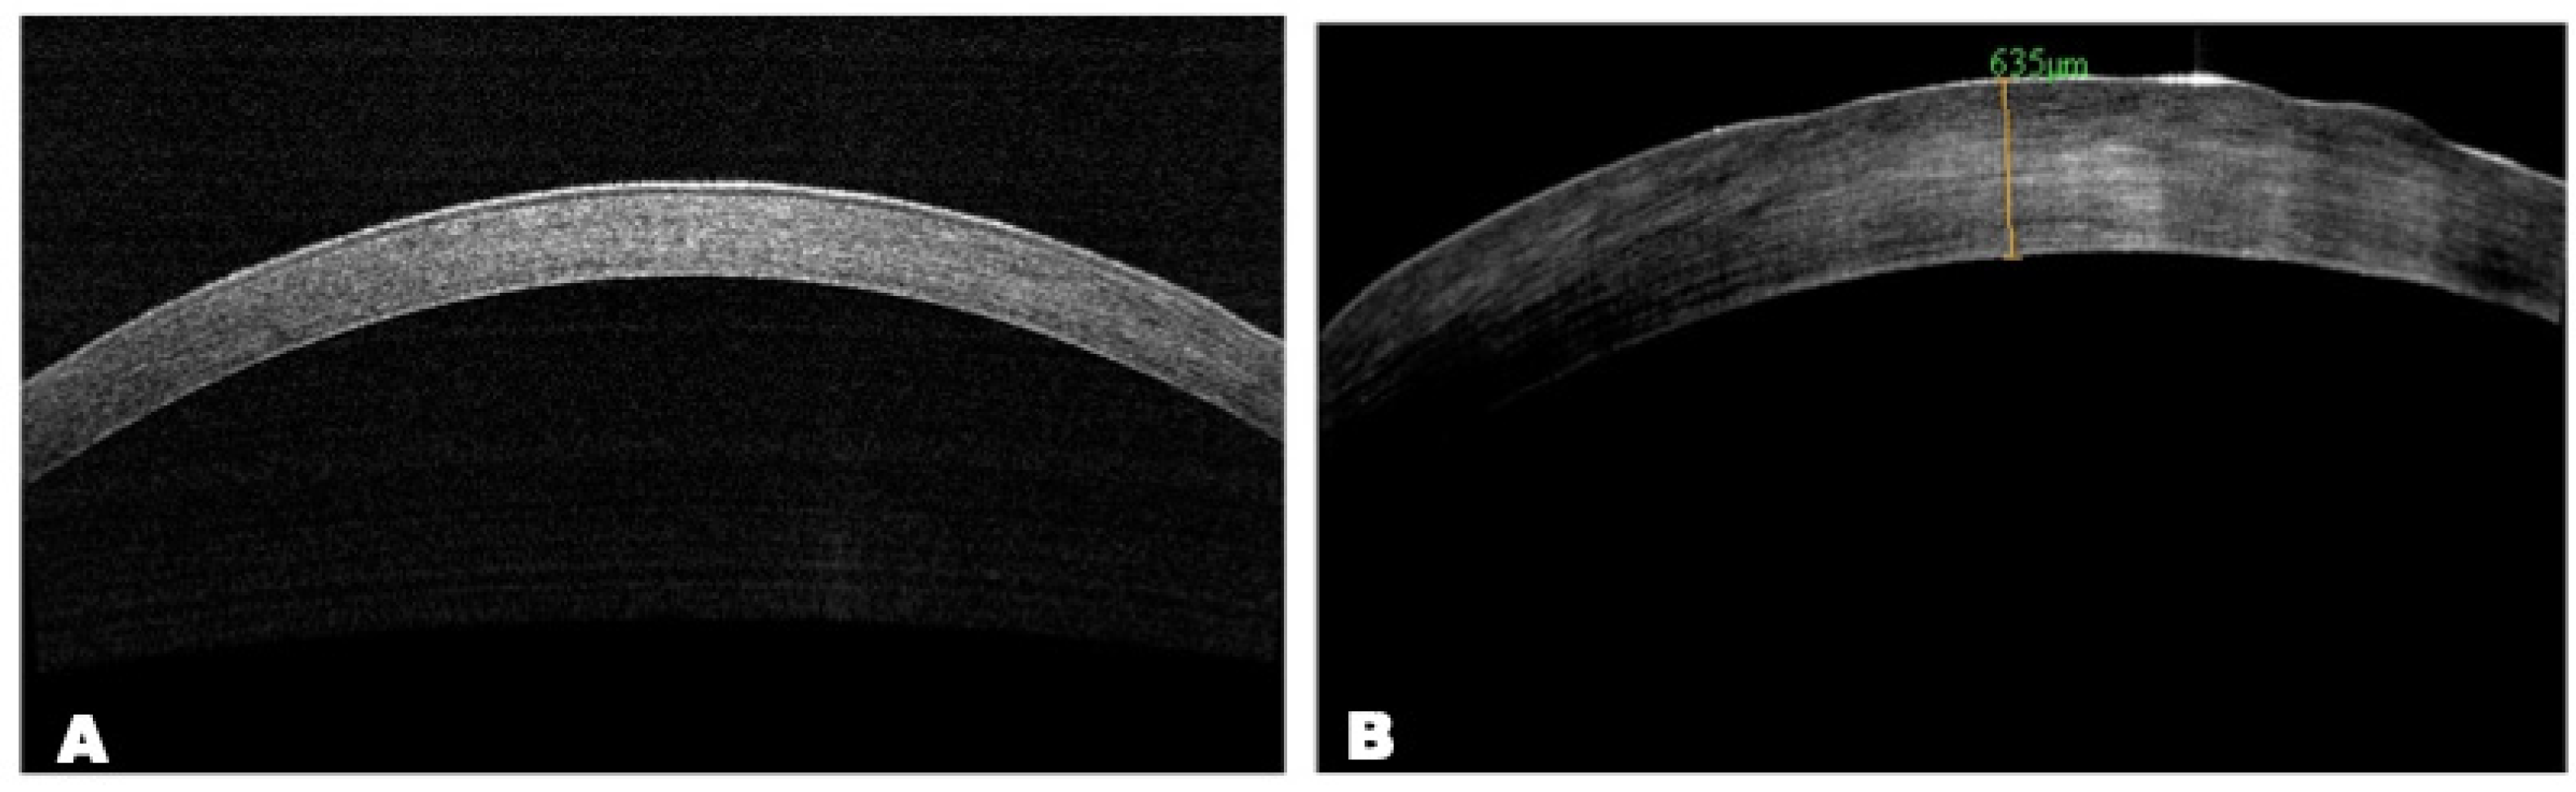

AS-OCT

AS-OCT data showed the presence of epithelial irregularity and stromal thinning with a hyperreflective area in the central zone of the cornea (Figure 9).

Figure 9. AS-OCT images. Scans of central cornea: (A) normal cornea; (B) AS-OCT scan shows area of anterior corneal haze with hyperreflective zone and epithelial defects; optical section is thickened due to corneal edema.

Biomedicines 12 00101 g009